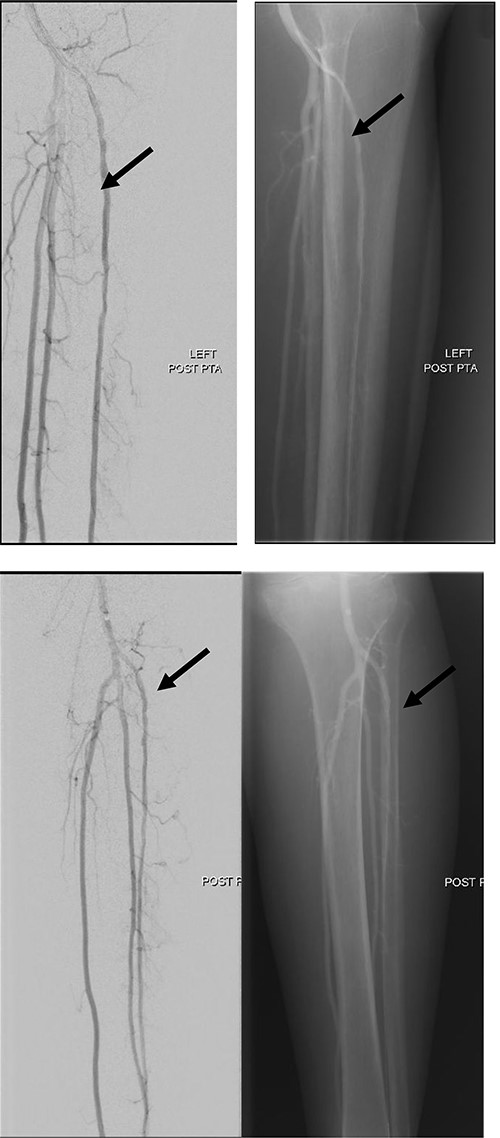

Good arterial flow of the ATA (arrow) after successful angioplasty and stenting.

Arterial flow noted at distal ATA and dorsalis pedis artery (arrow) after successful angioplasty and stenting.